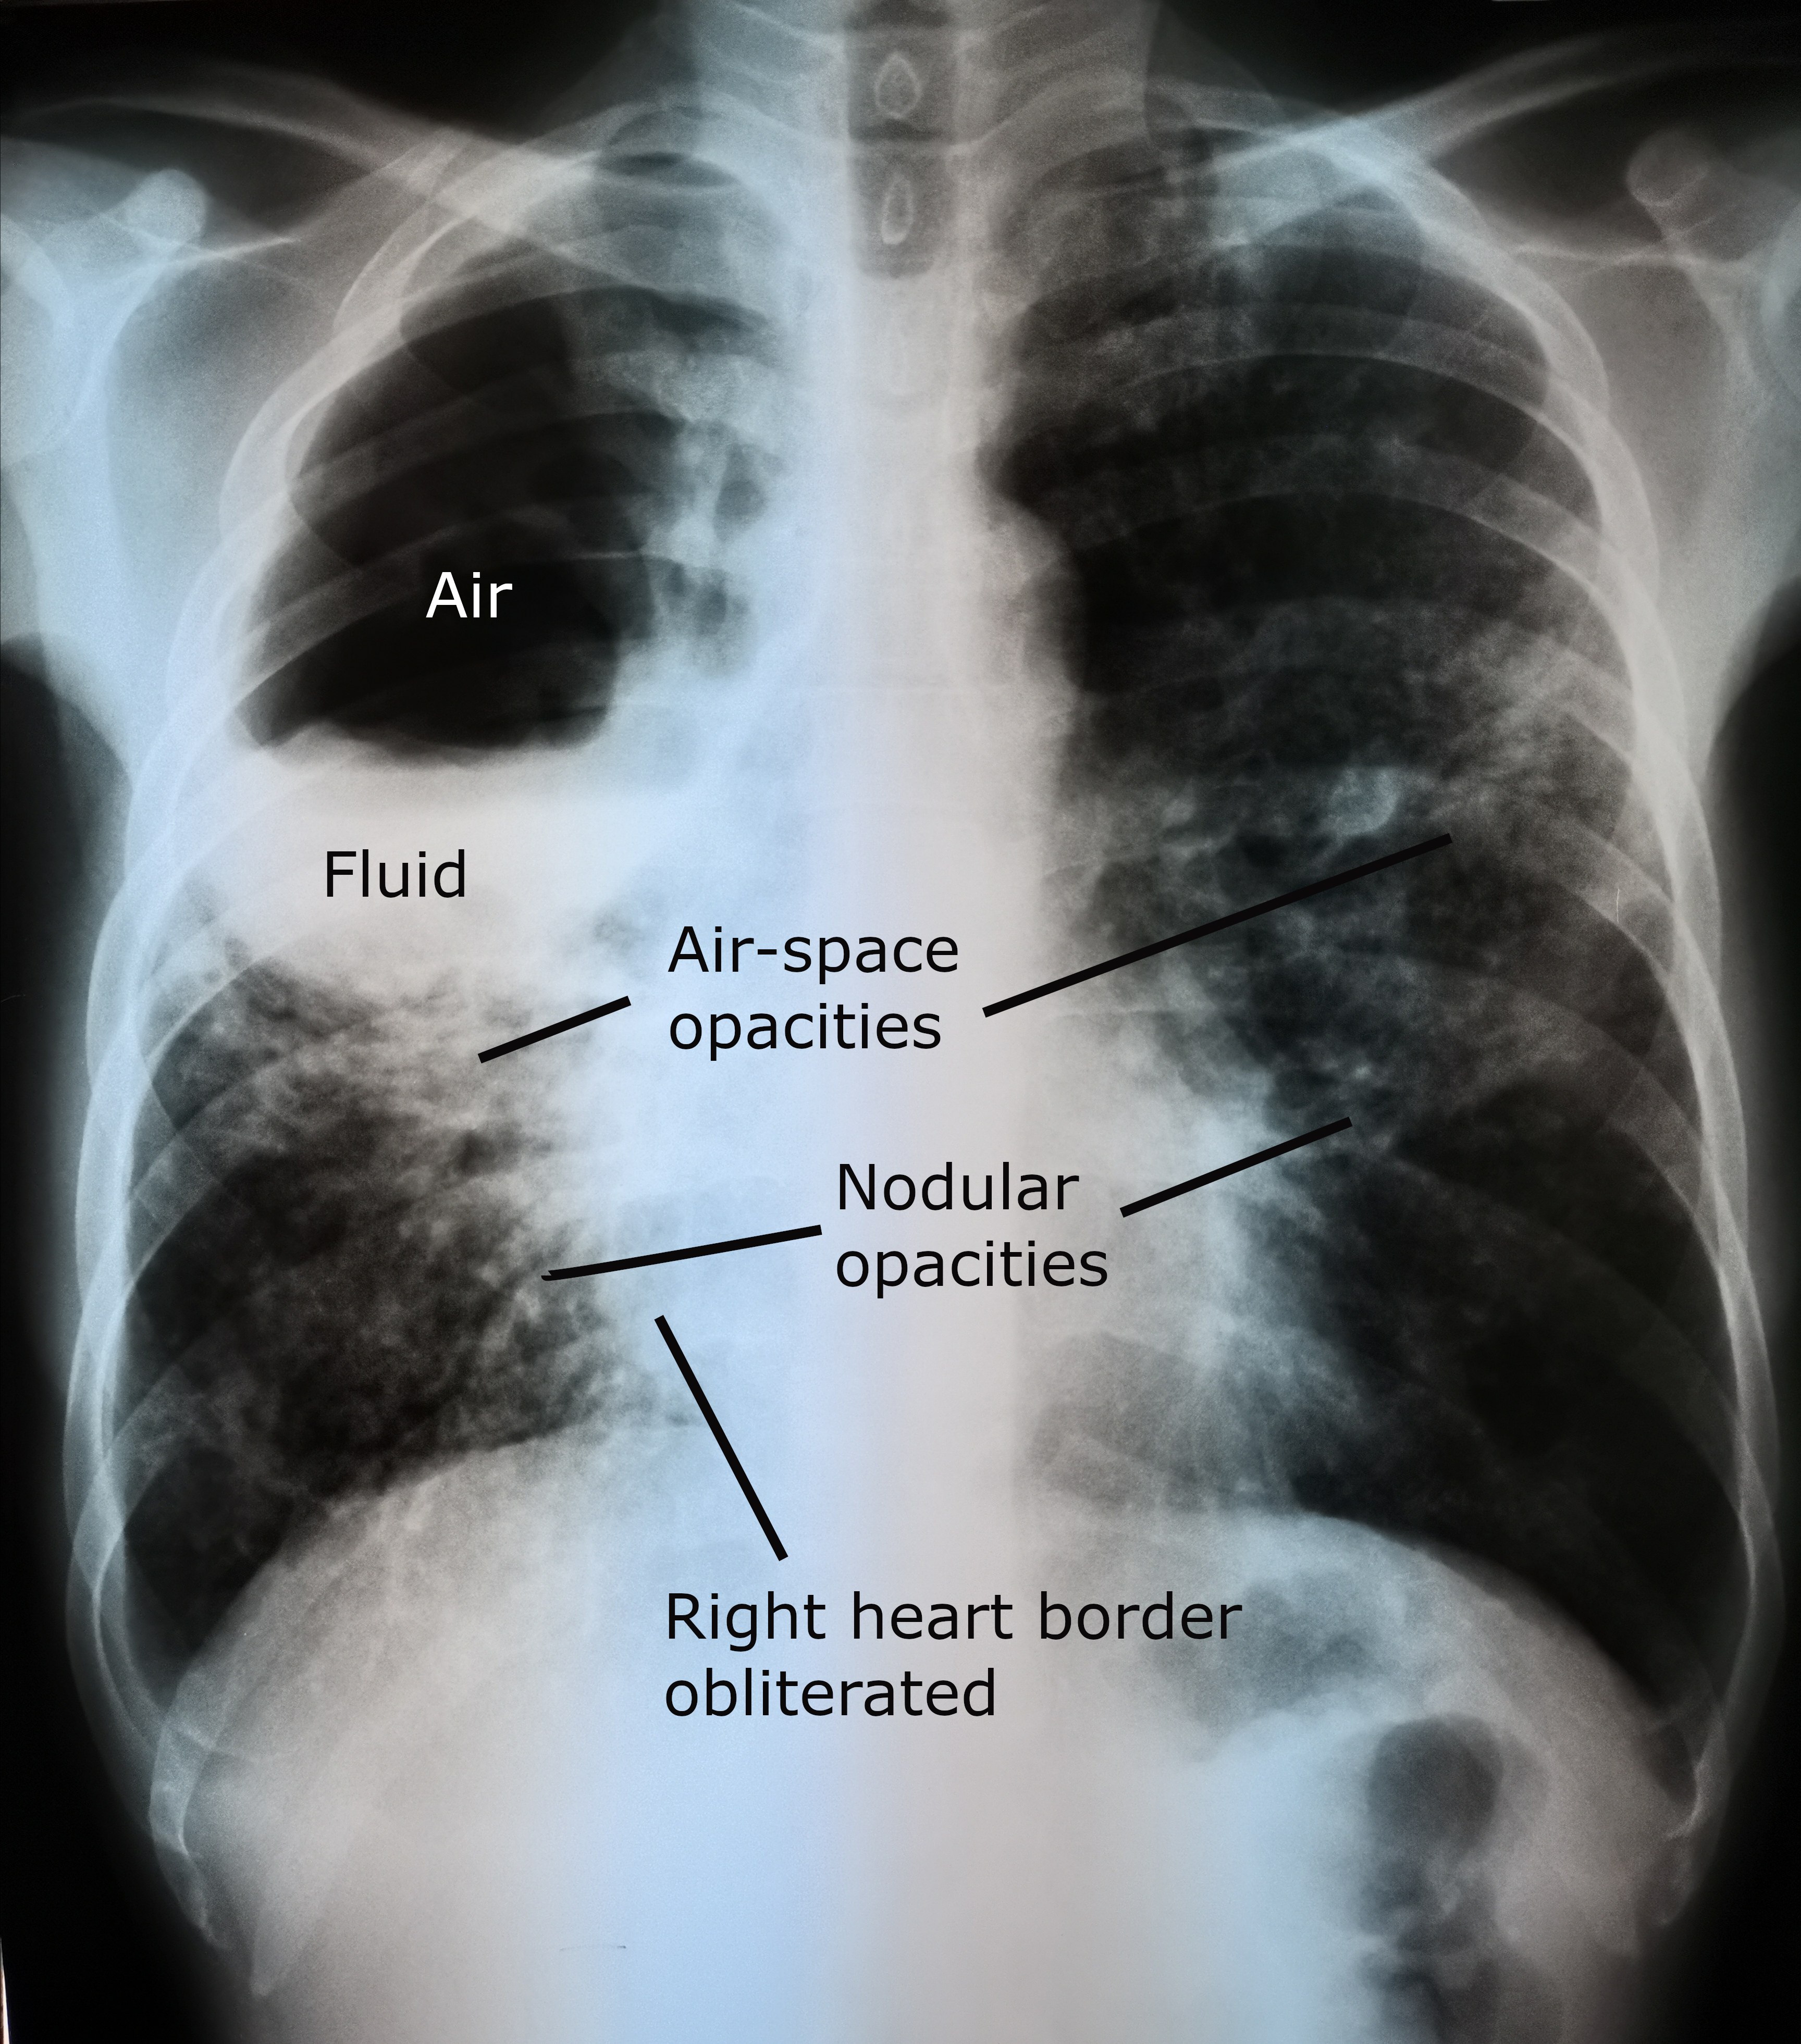

- Chest X-ray: consolidation early; classic rounded cavity with air-fluid level when communication with bronchial tree established

Necrotising pneumonia leads to liquefactive necrosis of lung parenchyma. Central necrosis liquefies and communicates with the bronchial tree, producing the classic air-fluid level cavity on imaging.